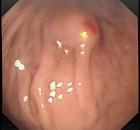

问题 男,23岁,食用海鲜后,出现腹痛、腹胀2天,呕吐,查体,无发热,下肢可见皮疹,B超肝胆正常,胃镜检查如图。最可能的诊断是 ( )

选项 A、阑尾炎 B、消化道出血 C、急性胰腺炎 D、过敏性紫癜 E、急性胆囊炎

答案 D